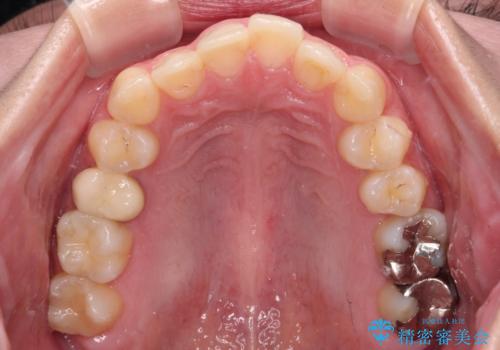

前歯のクロスバイト ギラギラのワイヤー装置で矯正治療

- 前歯のクロスバイトを改善したいとのことで来院された患者様です。

マウスピース矯正では前歯の神経への負担が大きいことを懸念され、ワイヤー装置による矯正治療を行うこととしました。

クロスバイトが改善する際は、前歯しか接触しないため、痛みがあったり食事が取りにくかったりと、不便な時期がありますが、1年強の短期間で無事に治療を終えることができました。